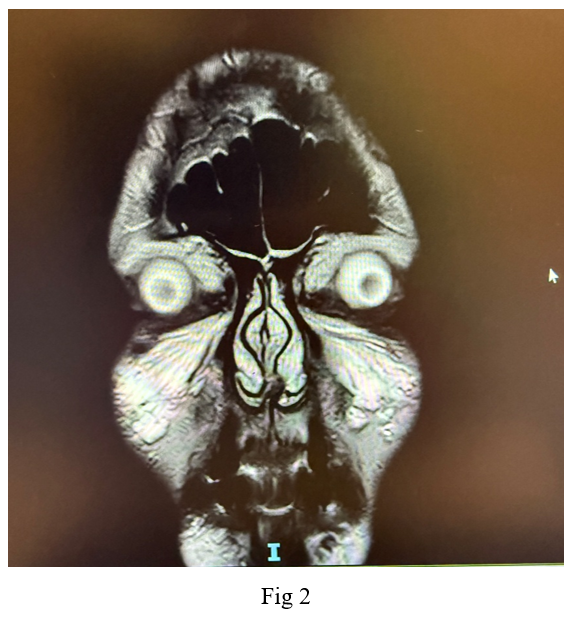

Imaging studies, including a native CT scan of the brain, MRI of the brain, and MRI of the orbit without contrast, revealed no pathological findings. Additionally, laboratory tests, including a complete blood count, erythrocyte sedimentation rate, C-reactive protein, fasting blood sugar, glycated hemoglobin, thyroid function tests, kidney function tests, B12 levels, blood glucose, and blood pressure, were all within normal ranges. Following a neurological consultation, he was diagnosed with cluster headache associated with oculomotor nerve palsy.

In this case, diabetic oculomotor nerve palsy was considered as a possible differential diagnosis; however, due to the classic symptoms of cluster headache and the fact that the MRI did not show any signs of inflammation or thickening of the oculomotor nerve in the cavernous sinus—characteristic of microvascular damage caused by diabetes—this differential diagnosis is unlikely.

Neuroimaging, such as Cranial MRI, is essential to rule out structural abnormalities, particularly in patients with symptoms resembling other headache types or conditions like pituitary tumors. Distinguishing cluster headaches from other trigeminal autonomic cephalalgias and primary headache disorders is crucial for appropriate management.

Figure 3